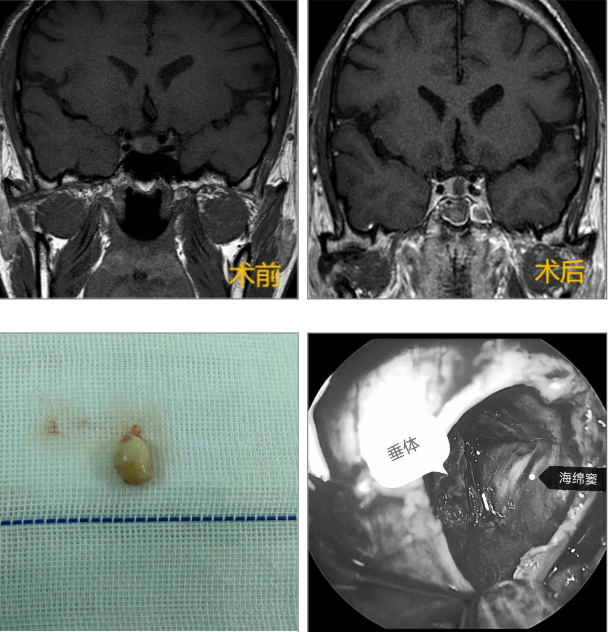

于某,体检发现鞍区占位1周。MRI提示垂体大腺瘤(3.0cm*2.7cm*2.3cm),Knosp:4级。术前泌乳素:17.57 ng/mL,皮质醇(08:00):116.9 nmol/L。术后第一天,PRL降至6.45 ng/mL,COR恢复至388.8 nmol/L,达到治愈标准。术后5天出院。